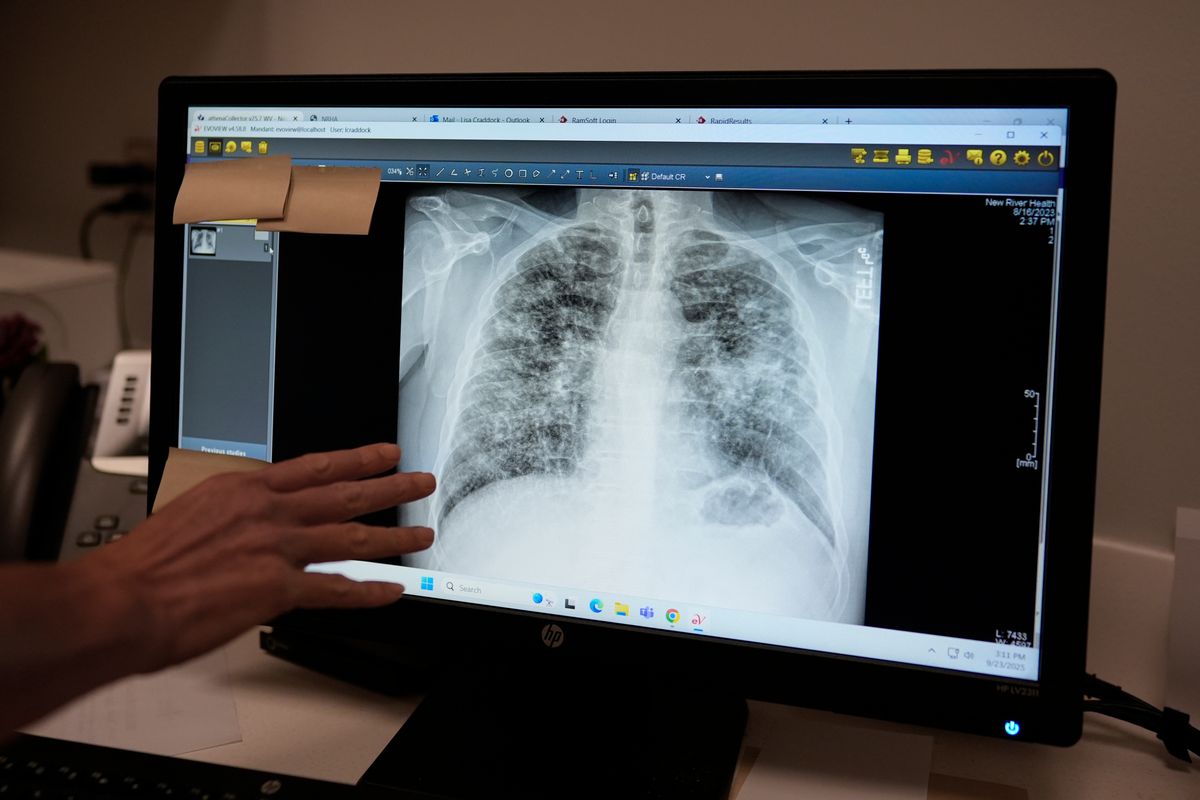

Experts say that’s because much of the easy-to-reach coal has already been extracted in West Virginia and neighboring Virginia and Kentucky, forcing miners to use massive equipment to eat through walls of quartz-filled sandstone to reach the remaining thin coal seams. This creates excess dust laced with shards of silica, which also cause lung cancer and kidney disease. It’s 20 times more toxic than coal dust, the major culprit of the past that often sickened older workers. The silica crystals embed in miners’ lungs, causing chronic inflammation and eventually irreversible scarring that peppers X-rays with chalky spots. It leaves proud, once-strong men skinny and weak. They choke on their food and gasp after just a few steps, cradling shiny cylinders that provide a lifeline of oxygen through tubes snaking into their nostrils.

From 1970 to 2016, more than 75,000 miners’ deaths were connected to black lung, according to NIOSH. Disease rates dropped after Congress put the agency’s Coal Workers’ Health Surveillance Program in place, but have surged since the late 1990s. NIOSH and unions have highlighted the need for the silica rule for decades, which cuts permissible silica dust levels inside mines from 100 to 50 micrograms per cubic meter of air averaged over an eight-hour shift — the same levels already enforced by the Occupational Safety and Health Administration in other industries such as construction. In 2018, NIOSH published a report showing around one in five coal miners with at least 25 years’ experience in central Appalachia had black lung. Those findings were based largely off of working miners who may not have been sick when X-rayed. Researchers say the newer numbers collected from black lung clinics like Emery’s show a bleaker picture because they capture miners who are disabled or retired, many of whom were never screened by NIOSH.

Emery said her youngest patient with the most complicated form of black lung, called progressive massive fibrosis, was just 31 when he was diagnosed after only 10 years underground. And he’s not alone: Rates in the region have jumped in recent years — hitting an all-time high for long-tenured miners in the mid-2000s, according to NIOSH data.

“What we’re seeing at the black lung clinics is just really alarming,” she said. “So truly, if the rule got put in place today, cutting the silica exposure level in half, you already have sick miners. It’s going to take a solid 15 to 20 years for us to start to see this taper off.”